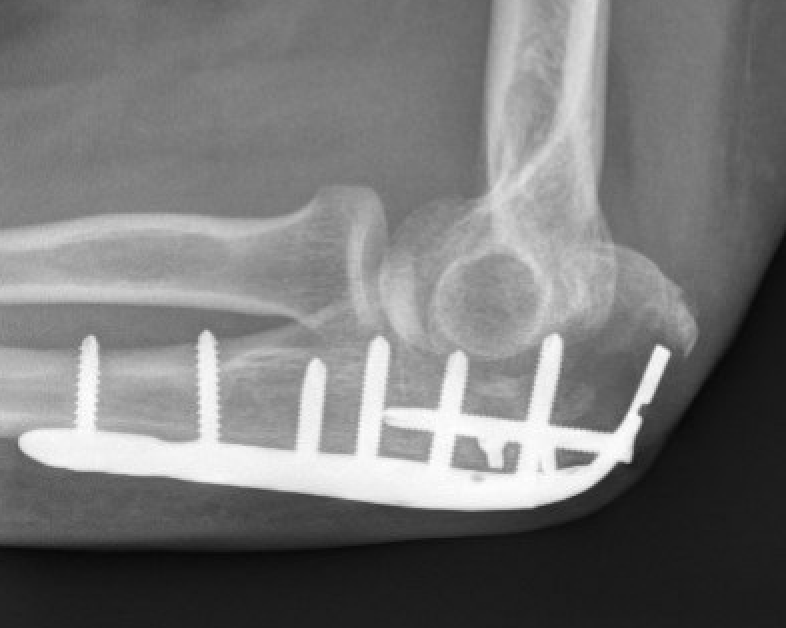

ORIF with olecranon plate

Indication

Fracture distal to center of rotation of elbow / trochlea

Technique

- use anatomical precontoured plate